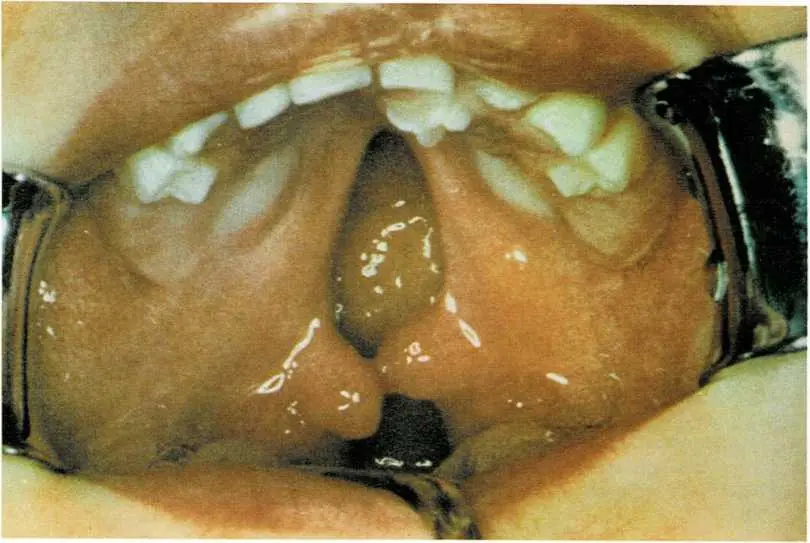

A cleft palate is a split in the palate (roof of the mouth). It is

present at birth.

Doctors sometimes use surgery to join the two parts of a cleft

palate.

Your physician may recommend surgery to correct the cleft palate, but

may delay surgery until the child is 2 years old. (See photographs on

page 205.) Or the doctor may suggest the use of a dental appliance